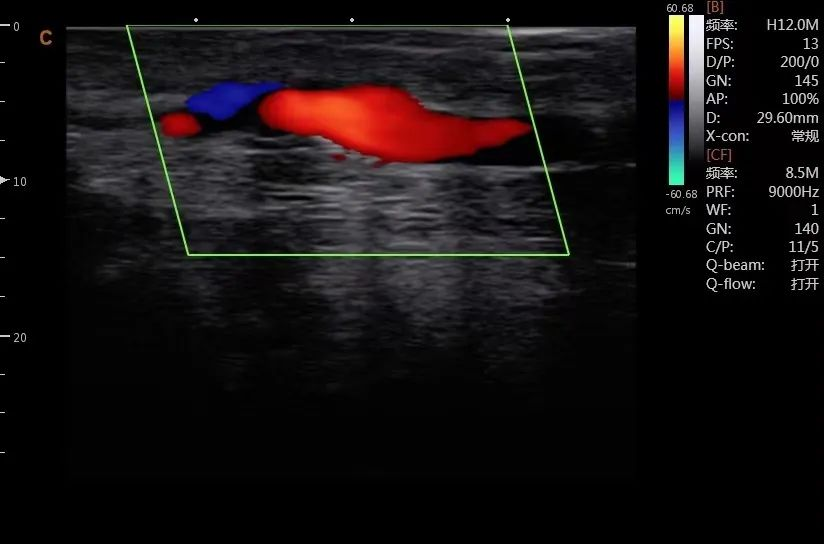

病例1:术后动静脉内瘘流出道静脉血流恢复,血流量230-250ml/min